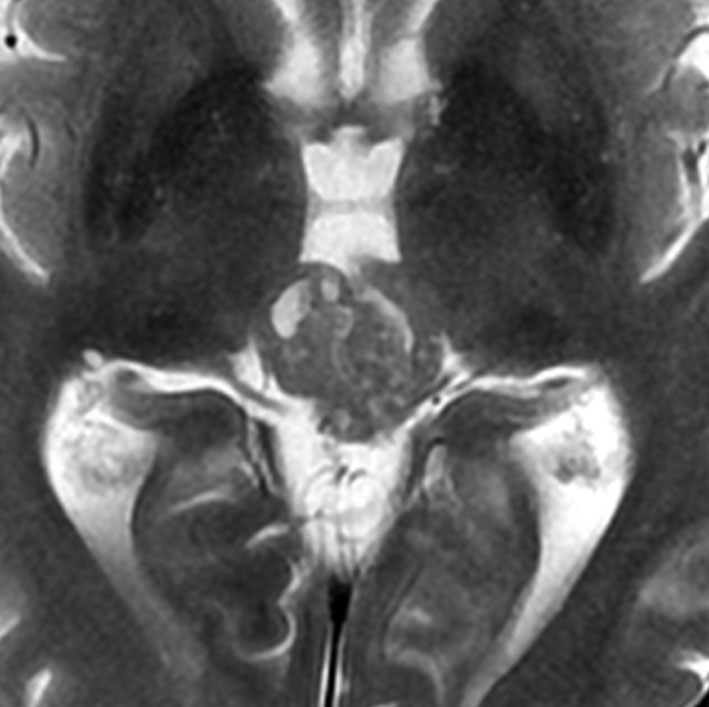

放射線化学療法後の画像です。腫瘍境界は不明瞭(左)で,腫瘍内出血(中央)して,左の視床に浸潤しています。かなりリスクは高いのですが,これを開頭手術で全摘出しました(右),この時点で完全寛解 CR です。この後にさらに化学療法と幹細胞移植(PBSCT,大量化学療法)が加えられました。